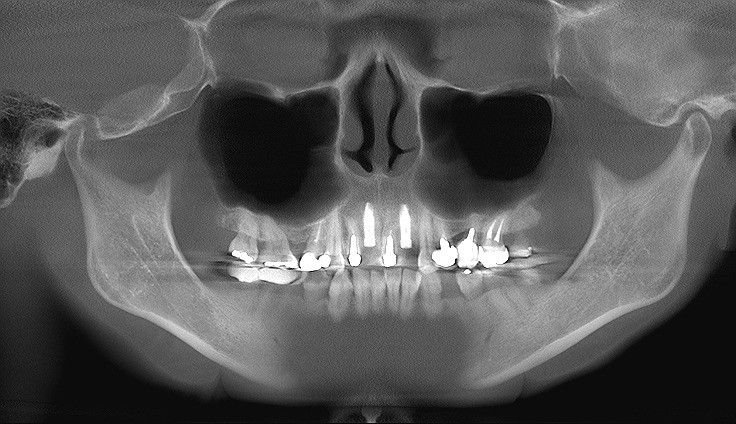

術後のパノラマになります

2本のインプラントを建てています

最終補綴はどちらも1,2の2連冠としています

残存歯の左上1番が少し支間長が長くなりましたが、、、

術前術後の矢状面レントゲンになります